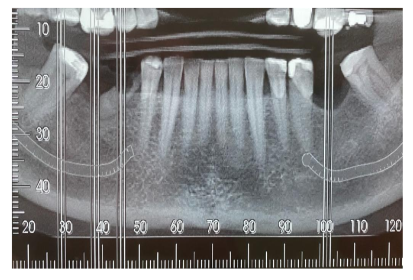

Paciente de 47 anos de idade, normossistêmico, apresenta indicação de extração do dente 45 e reabilitação por

implantes dos dentes 36, 45 e 46. De acordo com a imagem abaixo, constatou-se que: a distância do nervo

alveolar inferior em relação à borda alveolar é de 10mm na região do dente 45, 12mm na região do dente 46 e

13mm na região do dente 36. Além disso, a distância entre o dentes 47 e 44 é de 17mm e entre os dentes 37 e

35 é de 10mm.

Acerca do planejamento cirúrgico do paciente, qual das alternativas está correta?